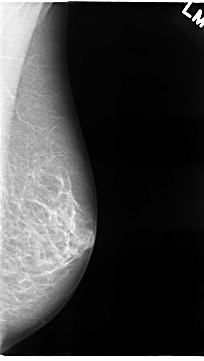

C_0069_1.LEFT_MLO

LEFT_MLO LINES 4688 PIXELS_PER_LINE 2648 BITS_PER_PIXEL 12 RESOLUTION 50 NON_OVERLAY